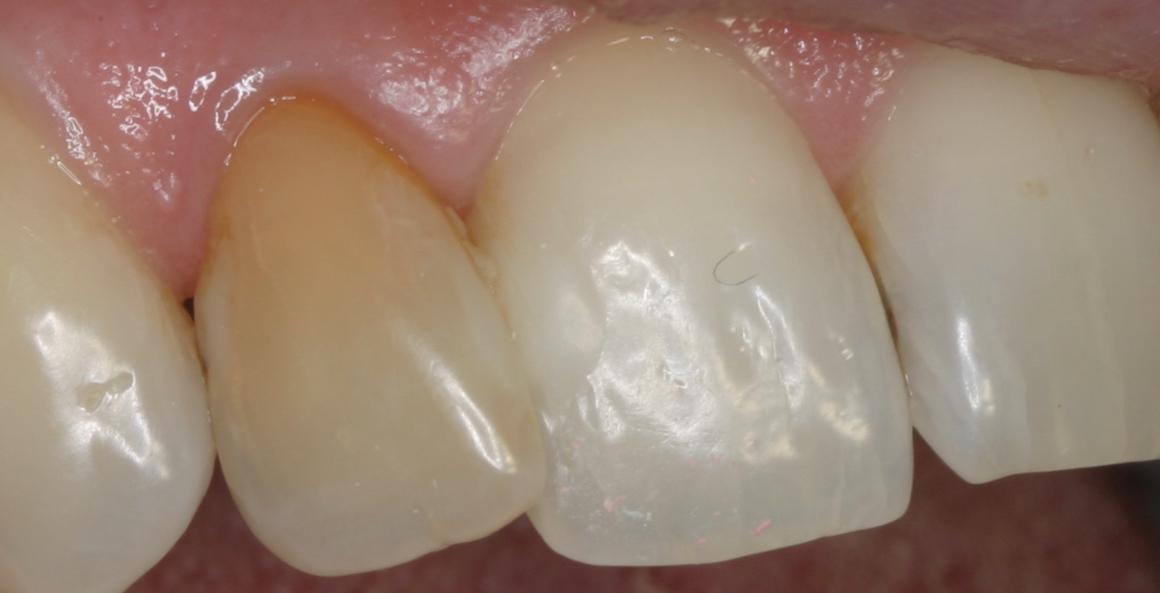

Discoloration due à un traitement de racine

Après 1 mois et 2 séances de blanchiment interne